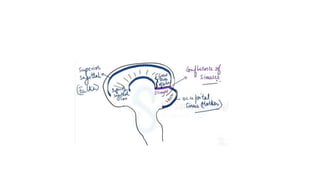

The document discusses lateral sinus thrombosis, also known as lateral sinus thrombosis or Otogenic suppurative thrombophlebitis, which is defined as the simultaneous presence of venous thrombosis and suppuration in the intracranial cavity. It is most commonly caused by b-hemolytic streptococcus and symptoms include nausea, vomiting, toxic and restless behavior, deep boring ear pain, and foul smelling blood tinged ear discharge. Management involves imaging, lumbar puncture of CSF to analyze volume, rate of formation, and composition.